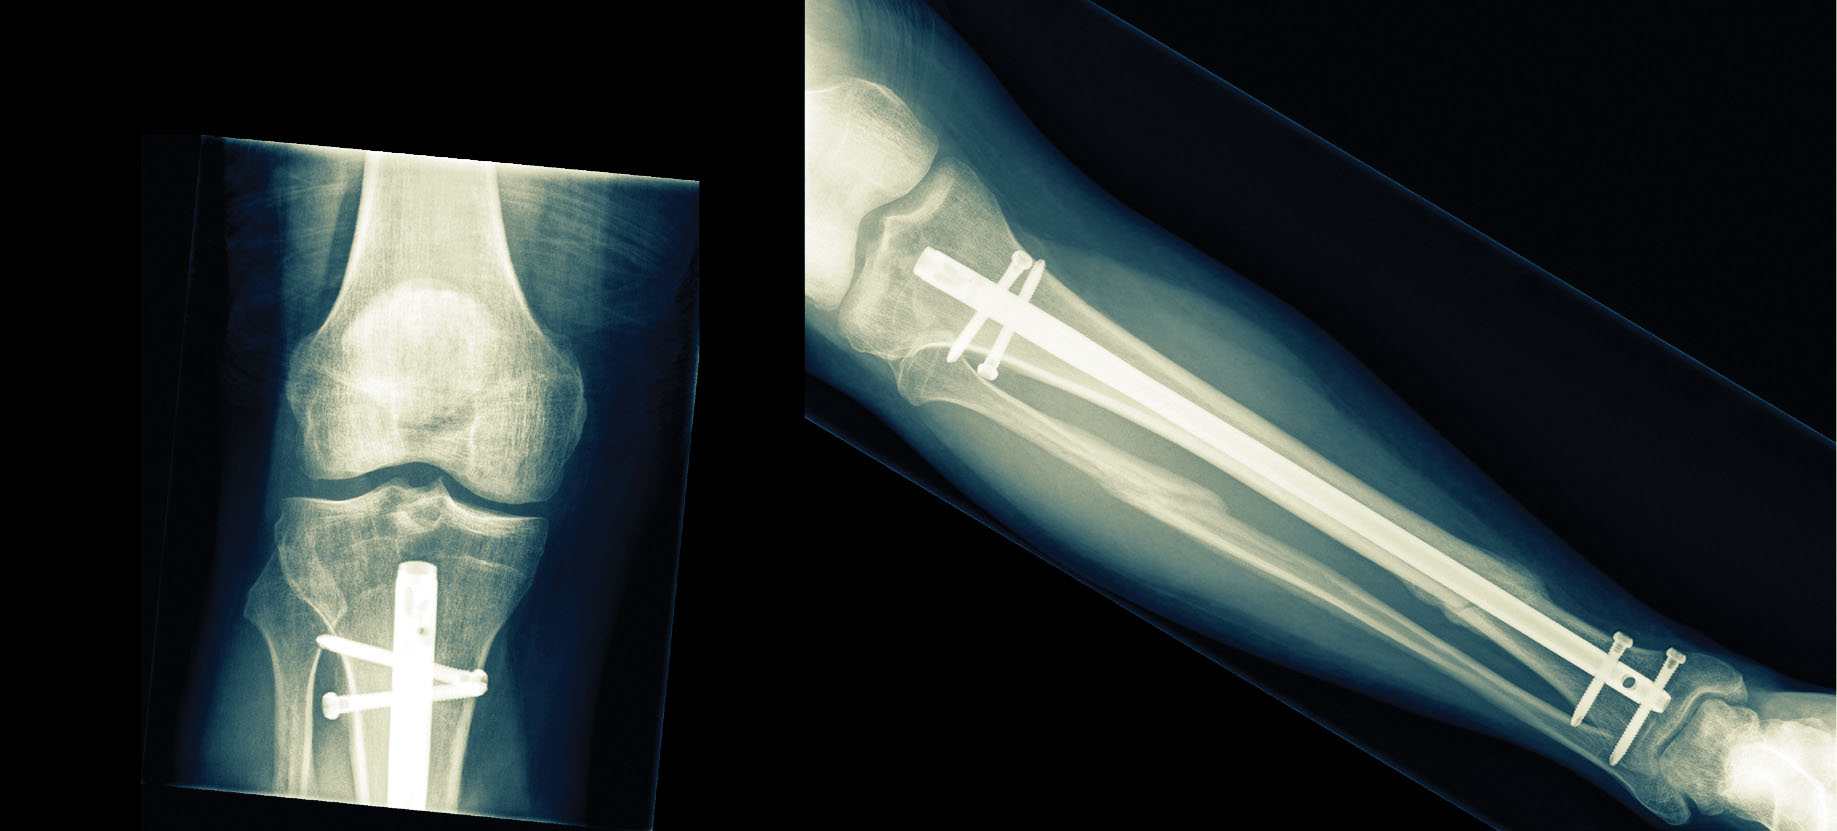

In adults, tibia (shinbone) fractures are usually fixed through the surgical implantation of a slender metal rod called an intramedullary nail in the hollow space within the bone. This treatment is generally effective for tibial fractures. However, in 10% to 15% of cases the bone fails to heal in a timely manner, resulting in a nonunion—or arrested healing.